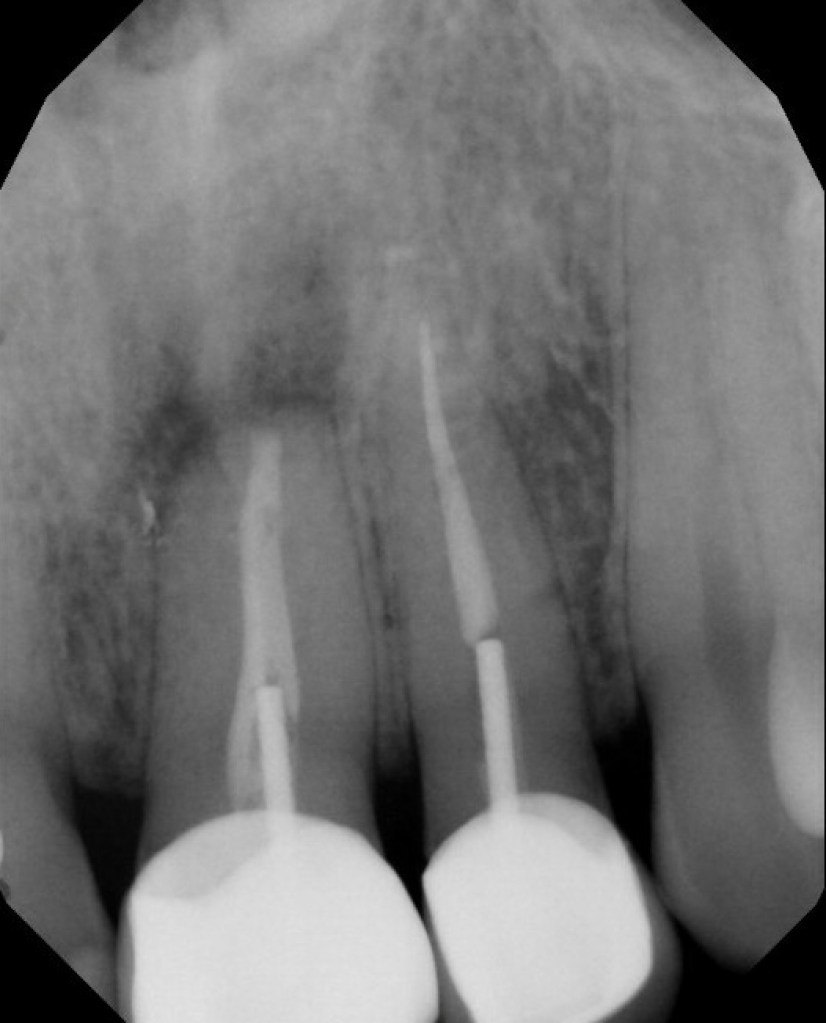

#21 NS-RCT

Dx: Pulpal Necrosis with SAP